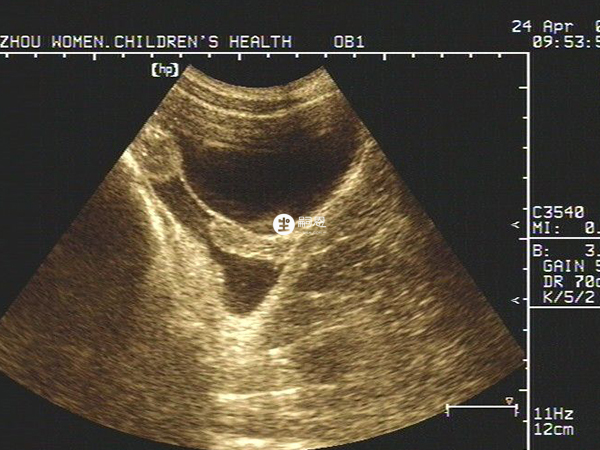

如果確定是基始子宮一般就不會再長大了。按說這個年齡一般乳房、外陰也應該開始發育,目前B超子宮至少是發育不良,建議查一下女性內分泌六項看看是不是發育晚,若是發育晚,那麼就還有可能會重新發育。但是具體能否重新發育因人而異,建議儘快進行治療,治療後看能否隨著青春期進行再次發育。如果青春期過了,或者是已經成年的話,那子宮就不會再發育了。